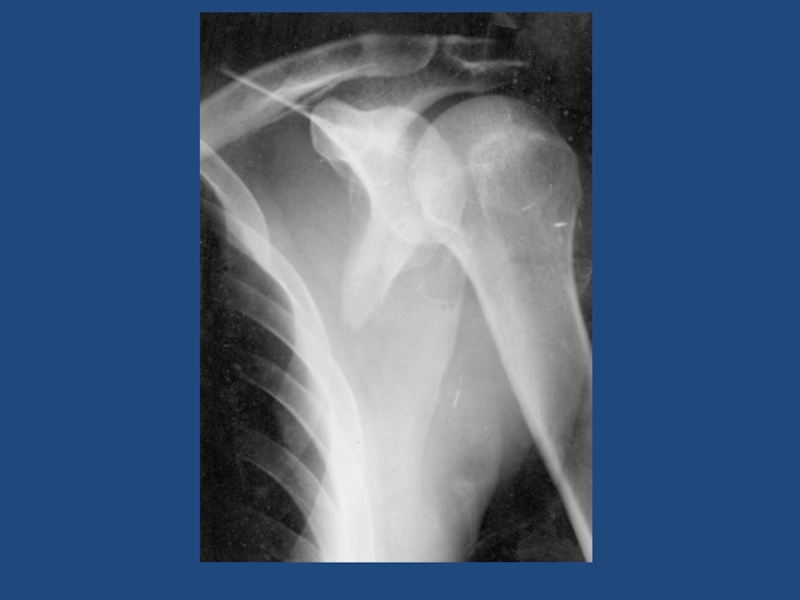

Слайд 2423

Передне-нижний вывих плеча подклювовидный?

23Передне-нижний вывих плеча подклювовидный?